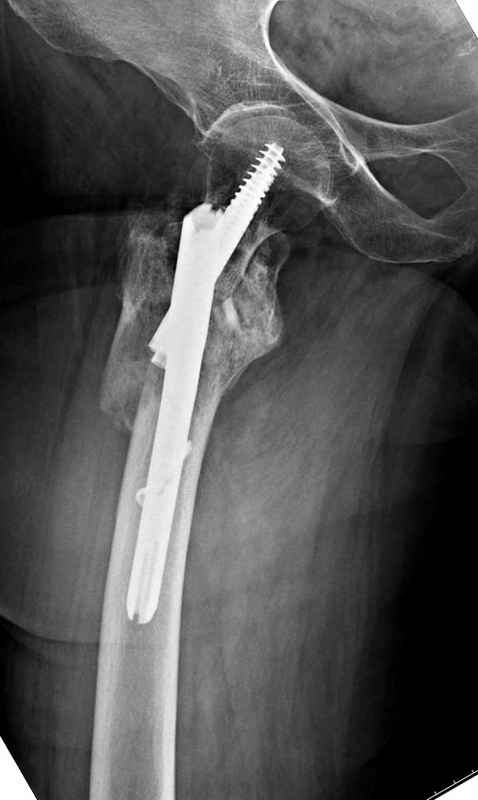

Из фиксаторов, мы бы применили цефаломедуллярные, потому что они "по закону моментов" из-за короткого рычага от центра головки к диафизу и по принципу "головка диафиз" механически лучше выдерживают нагрузки, чем пластины.

Но современные пластины с угловой стабильностью не отстают от медуллярных конструкций. Межфрагментарные шурупы и имплант как нейтрализирующее создаст адекватную фиксацию.

Здесь пара случаев фиксации похожих переломов:

первый высокоэнергетическая травма 36 лет